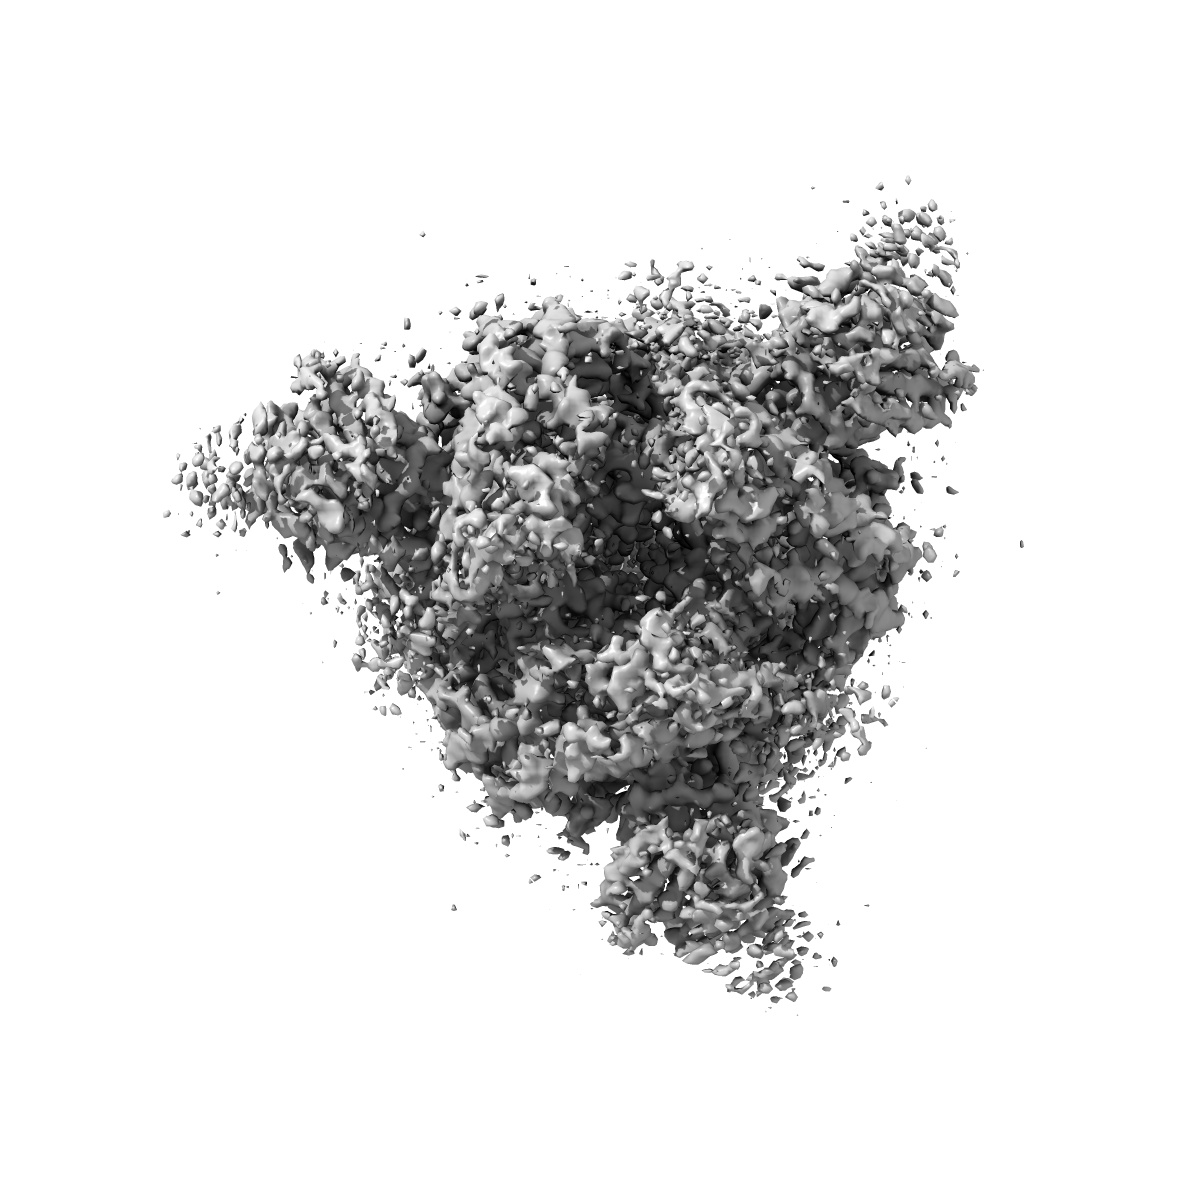

Structure of Covid Spike variant deltaN135 in fully closed form

Single-particle3.21 Å

Sample: Covid Spike variant deltaN135